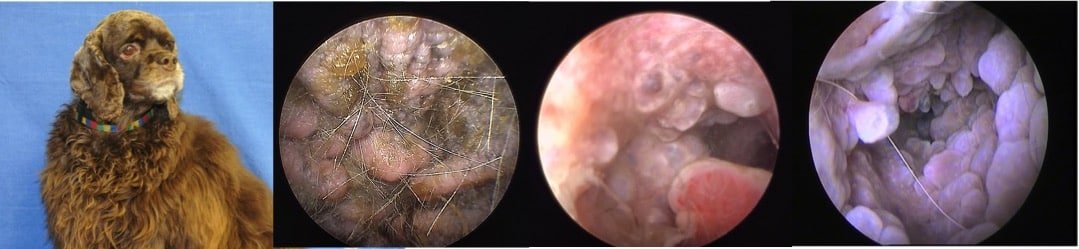

L’hyperplasie primaire des glandes cérumineuse est une des plaies du cocker américain, générant des otites…